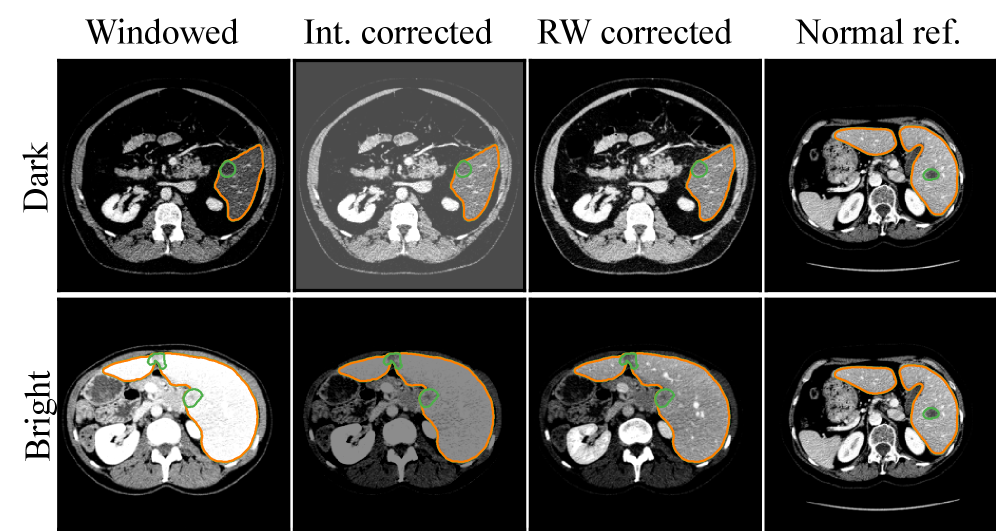

Although CT scans are obtained with similar protocols, variations due to contrast-enhancement are expected. In 3(a), ”Windowed” and ”Normal ref.” display how the same clipping setting can result in different liver brightness in CT images due to contrast-enhancement.

As Random windowing introduces variation to the CT clipping during training, it enables scans to be visualized in multiple ways, which can result in better visualizations. Intensity augmentations that transform clipped HU distributions will struggle to create the same variation.

In 3(a), we aim to remedy the poorly timed contrast-enhancement using standard intensity augmentations and Random windowing. Standard augmentations cannot correct the loss of detail in the image, while the Random windowing settings yield a much better result. Additionally, standard intensity augmentations transform all values equally, and the background and bone structures, like the spine, outside the soft tissue range, are artificially darkened/brightened and can be considered artifacts in the final image.

Refer to caption

(a) Improving visualization of difficult scans.

(b) Simulating scans with non-standard contrast-enhancement.

Figure 3: Comparison of Random windowing and intensity augmentations. Random windowing samples beyond default window boundaries, improving visualizations during training, and recovering information lost with standard augmentations. It also produces realistic, challenging samples without the artifacts introduced by standard intensity transformations.